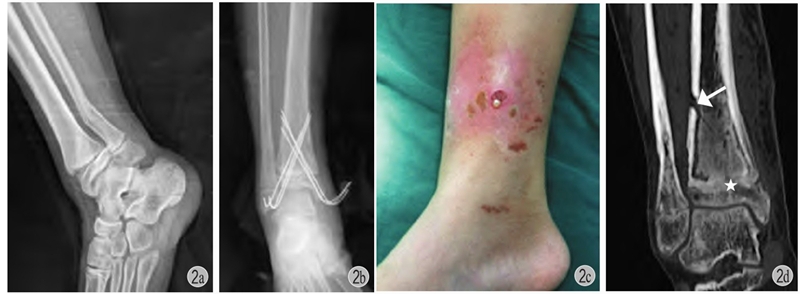

(1)一般来说小年龄患儿的干部骨折不需要切开复位内固定,以股骨干为例,4岁之前通常不用内固定治疗,4~10岁之间通常选用弹性针固定,11岁以上一般考虑青少年锁定髓内钉(图3)。

图3 患儿,男,7岁

a、b:左股骨干骨折,应尽量闭合复位应用弹性针或肌肉下接骨板固定,该患儿切开复位,局部螺钉+外架固定;c:拆除外架后3个月发生再骨折